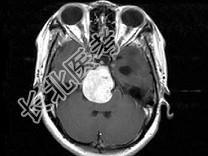

- 单项选择题女,32岁, 头痛、右侧肢体功能障碍约1年,声音嘶哑, 饮水呛咳,根据所提供图像, 最可能的诊断是 ( )

A、(斜坡)脑膜瘤

B、(斜坡)脊索瘤

C、(斜坡)神经鞘瘤

D、(斜坡)软骨瘤

E、(斜坡)海绵状血管瘤